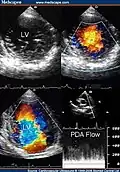

Trabeculation of the ventricles is normal, as are prominent, discrete muscular bundles greater than 2mm. In non-compaction there are excessively prominent trabeculations. Echocardiography is the reference standard for diagnosing NCC, although it can be well defined by computer tomography scan, positron emission tomography and magnetic resonance imaging.[13] Chin, et al., described echocardiographic method to distinguish non-compaction from normal trabeculation. They described a ratio of the distance from the trough and peak, of the trabeculations, to the epicardial surface.[14] Non-compaction is diagnosed when the trabeculations are more than twice the thickness of the underlying ventricular wall.